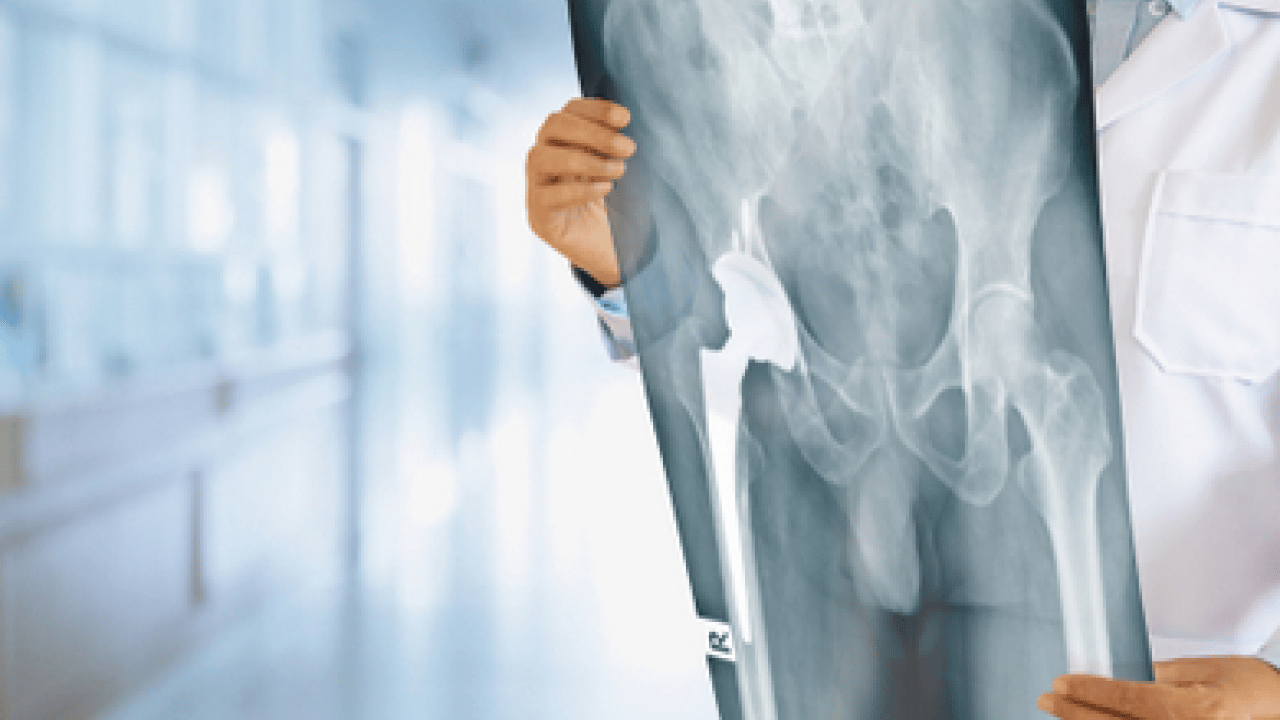

KTÜ Farabi Hastanesi Ortopedi ve Travmatoloji Bölümü’nden Doç. Dr. Muhammet Salih Ayas, kemik tümörlerinin tedavisinde erken teşhis ve doğru cerrahi planlama sayesinde günümüzde birçok hastada uzuv kaybının önlenebildiğini söyledi.

Kemik tümörü cerrahisinde önemli bir dönüşüm yaşandığını belirten Ayas, bu gelişmenin hem cerrahi tekniklerdeki ilerlemeler hem de tanı yöntemlerindeki hassasiyet artışıyla mümkün hale geldiğini ifade etti.

Ameliyat sonrası oluşan kemik ve doku kayıplarının modern rekonstrüksiyon yöntemleriyle başarıyla giderilebildiğini ifade eden Ayas, "Biyolojik teknikler, hastaya özel geliştirilen protezler ve kemik transferleri sayesinde hem anatomik bütünlüğü yeniden sağlıyor hem de hastalarımızın fonksiyonlarını en iyi şekilde korumayı hedefliyoruz" diye konuştu.